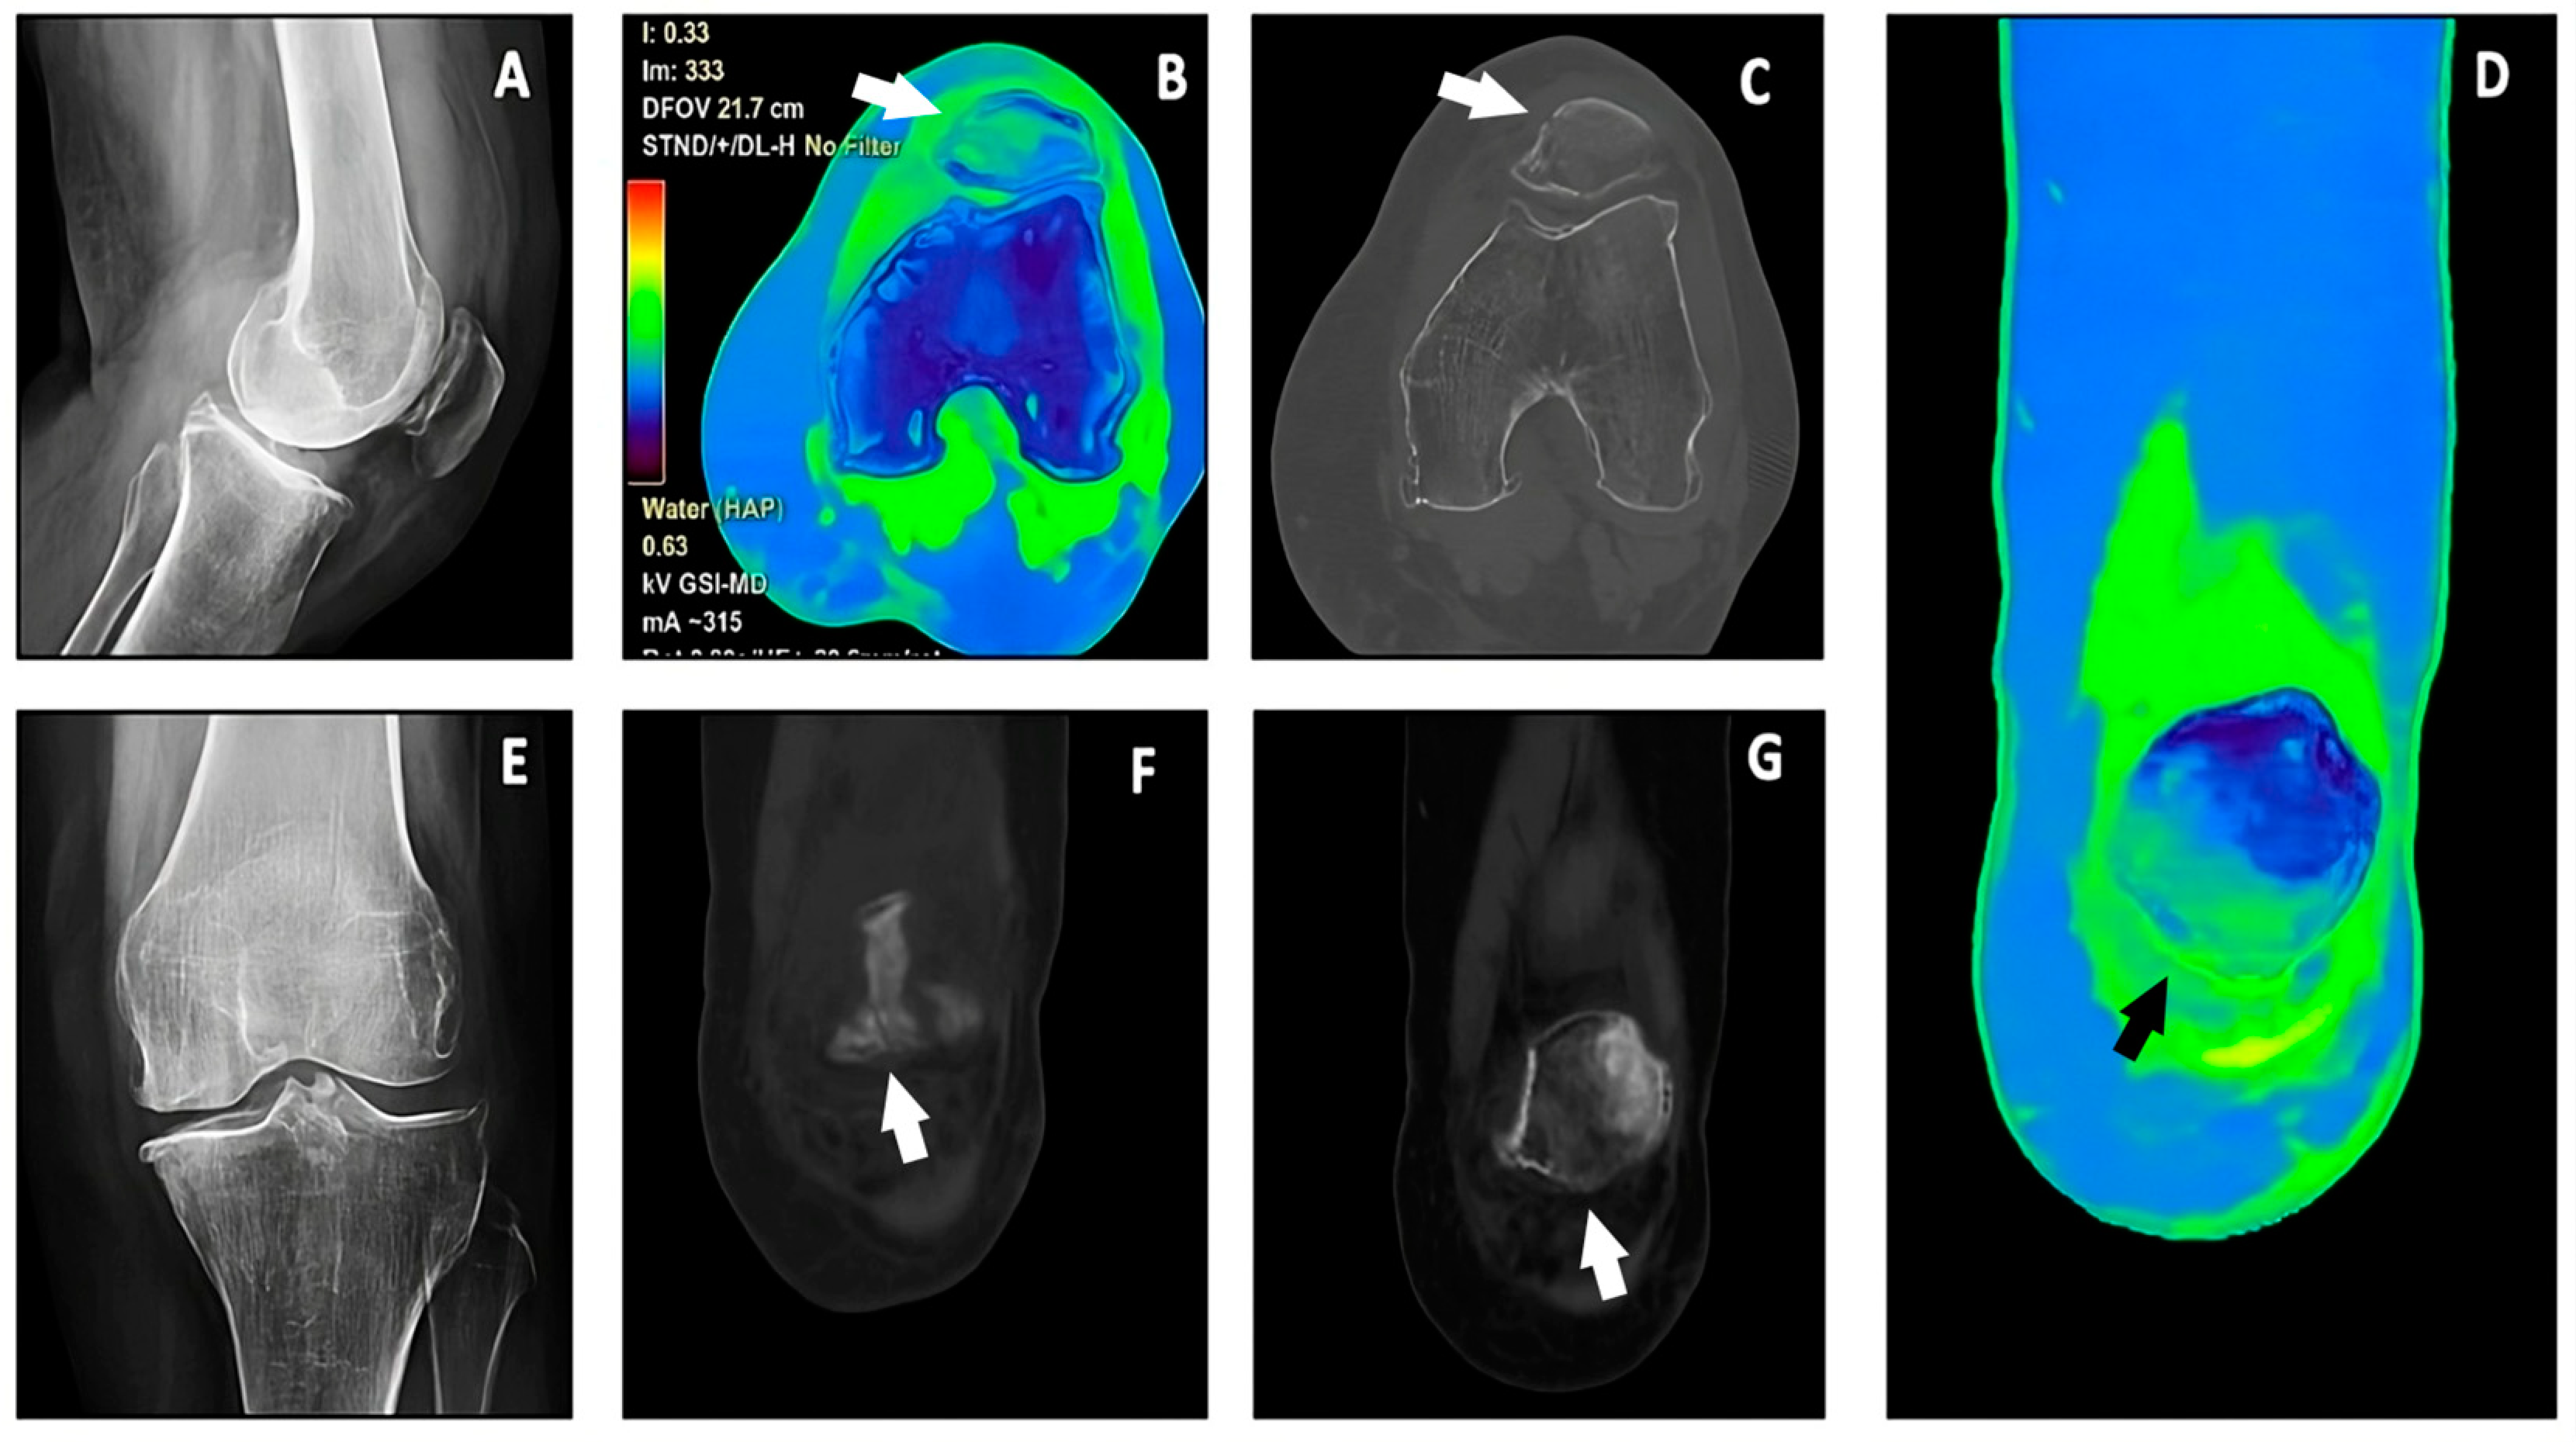

Toward the Application of Dual-Energy Computed Tomography with Virtual Non-Hydroxyapatite Color-Coded Maps to Identify Traumatic Fractures in Daily Emergency Settings

3. Results